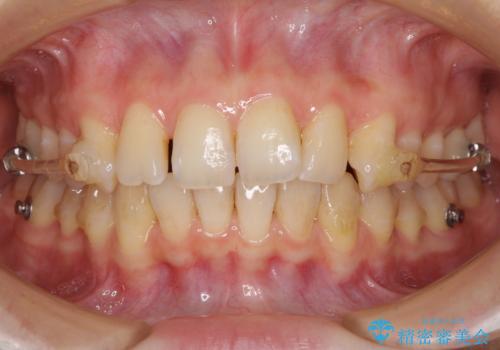

口元の閉じにくさを改善するためには、上顎臼歯を後方に移動させた咬み合わせにする必要があります。

インビザライン単体で改善することも可能ですが、達成する可能性が高くないため、カリエールディスタライザーという補助装置を併用して、より確実性を上げることとしました。

奥歯の咬み合わせを改善しながら、並行してインビザラインで歯列を整えることとしました。